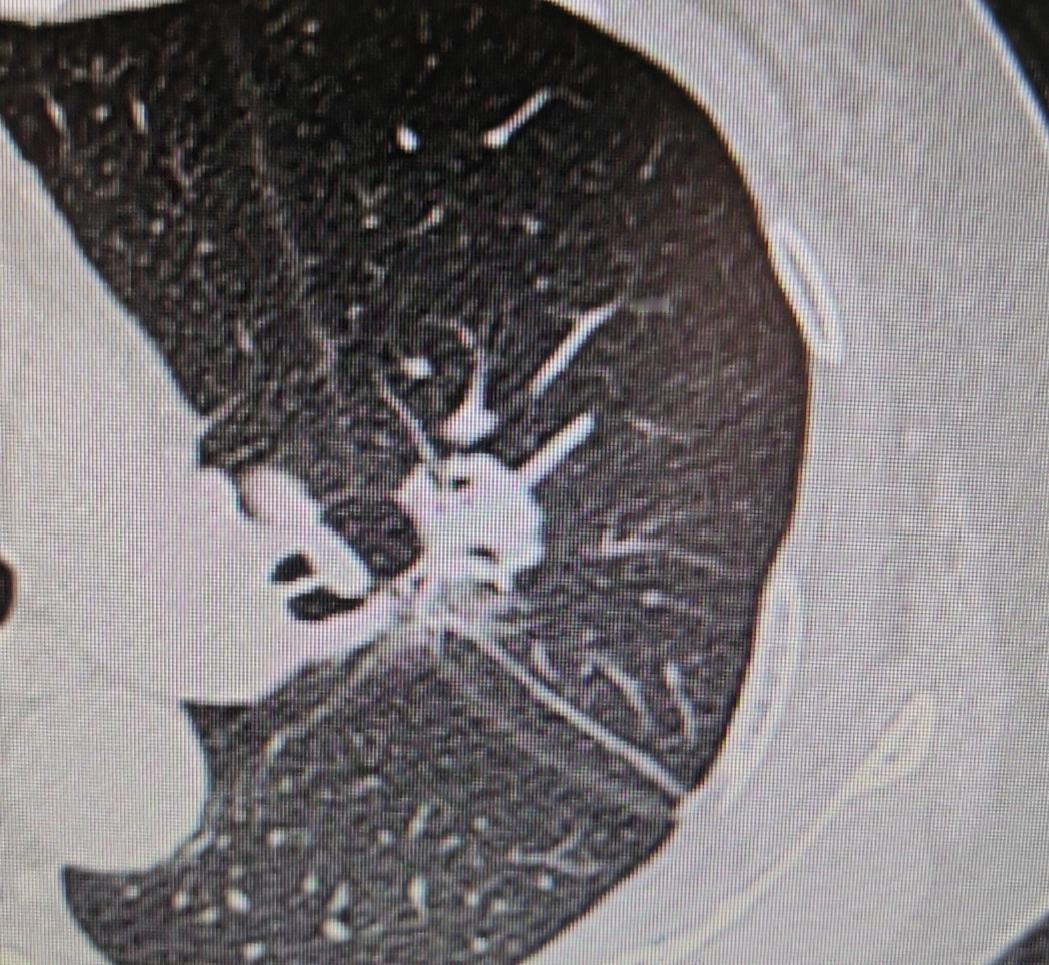

给大家分享一个特别的病例,这位65岁的女性患者,最近两个月,全身关节总是酸痛,而且越来越严重。幸好她有位亲戚是医生,就建议她做个全面体检。 这一查,果然发现了问题——肺里长了一个肿瘤,同时还请了风湿免疫科的医生会诊,也判断她有风湿方面的问题。 又做了进一步检查考虑是肺癌,幸运的是,全身检查下来没有发现转移。我们很快为她安排了手术,术后病理也证实了是“浸润性腺癌”。 手术过程倒是挺顺利,不过这位患者的肺部结构确实和一般人不太一样——她的左上肺叶自然分成了两叶,也就是固有段和舌段分开的。这种情况真的很少见,可能一百个人里也难找到一个。 另外,她的肺动脉有五支分支,走形也不典型,舌段的动脉是从气管前方走的。好在手术顺利完成,没有受到这些变异的影响。 最让人意外的是术后第二天,我们查房时问她关节还痛不痛,她说:“奇怪,好像不痛了。” 这其实就印证了这是“副癌综合征”的表现——肿瘤分泌的特殊物质进入血液循环,引起关节酸痛等症状。随着肿瘤被切除,症状也就自然缓解了。 这个病例提醒我们,当身体出现不明原因的关节疼痛时,除了考虑风湿免疫类疾病,也要警惕可能是肿瘤发出的信号。 特别是当常规治疗效果不好时,一定要做全面检查,找出真正的病因。[作揖][玫瑰]